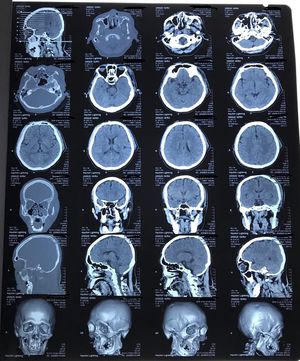

A 54-year-old man, pedicab driver, was hit from behind by a car while riding a pedicab. He had a multiple vulnus appertum at his scalp, face, and left arm. He had no loss of consciousness, no vomiting, no nausea. Rhinorrhea +/+, otorrhea -/-. GCS E4V5M6, BP 110/70, HR 67 bpm, RR 16 bpm, temp 36,7 degrees celsius. His neurologic examination, including memory, is normal. His head CT is shown above. Can you see fracture on that head CT?

Fracture seen in lt maxila ( anterior and medial wall)